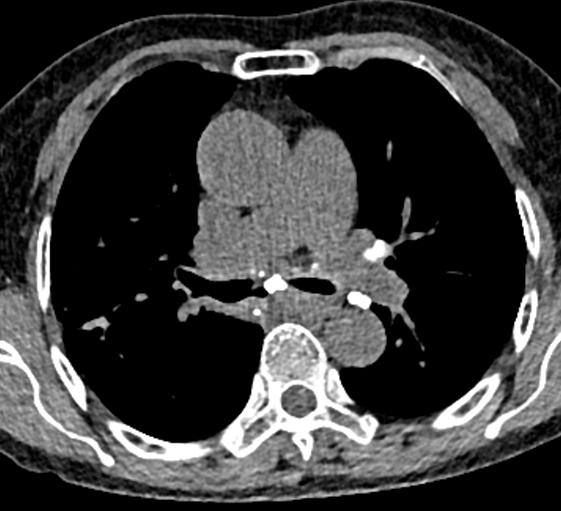

另外,这个患者的钙化灶非常危险,因为钙化灶的一端距离肺动脉才2毫米左右(图17),支气管镜下强行牵拉钙化病灶很可能会大出血危及生命。

图17 胸部CT

明确诊断及治疗都需要支气管镜检查,肿么办?改全麻下行硬质支气管镜检查。